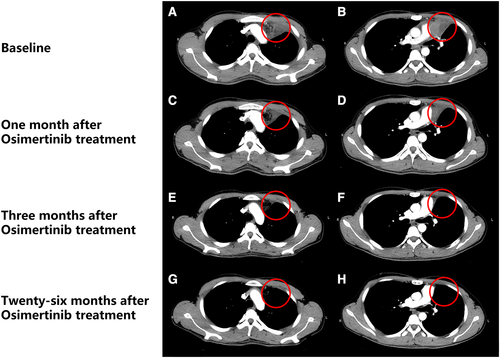

患者2017年6月份检测到EGFR T790M胚系突变(并携带L858R体系突变),随后于2017年6月28日开始口服奥希替尼治疗。一个月后,患者的心包和左胸腔积液被吸收,肺淋巴结变小,三个月后,患者的症状进一步改善,根据RECIST v.1.1标准,临床反应被分类为完全缓解(CR)。患者接受奥希替尼治疗30个月(至2019年12月),并没有出现与药物有关的重大不良事件。

▲ 奥希替尼治疗后的影像图